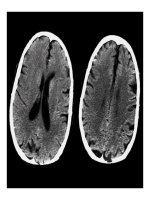

TRIỆU CHỨNG HỌC:

Bất thường hình thái giải phẫu.

Tổn thương:

Vò trí tổn thương

Đậm độ tổn thương trước và sau chích thuốc cản

quang.

Hiệu ứng choán chỗ

Phù não